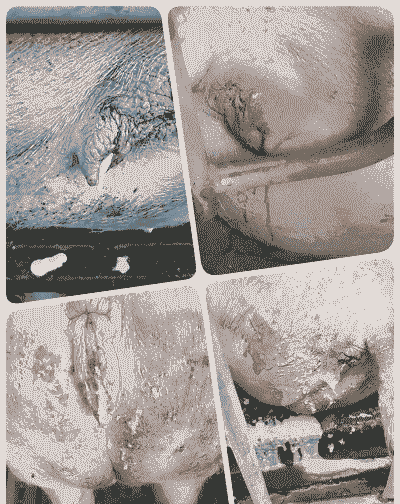

产道损伤 :母猪在生产过程中,外阴可能会肿胀后破裂或阴户撕裂,导致动脉血管断裂,从而引起大出血。此外,助产时如果损伤了产道或老龄母猪子宫脆弱,也可能导致产道内出血。

母猪在分娩过程中,子宫可能会受到损伤,如子宫复位不全,导致子宫内出血。

产后出血往往是由于血管破裂造成的。如果能够用外科方法找到出血的血管并进行有效的结扎,治疗效果最好。如果找不到出血血管,可以使用收敛药物在出血部位进行涂抹,同时肌注止血药(如止血敏)。

首先,应迅速采取措施止血,如使用缝合止血、填塞纱布块压迫止血,并立即注射止血敏和葡萄糖酸钙。

另外,针对可能存在的感染或炎症,可以使用抗生素或其他药物进行治疗,如氯前列希醇、宫净康、鱼腥草、头孢噻呋钠等。

在助产过程中,应注意剪指甲、涂润滑剂,尽量减少对产道的损伤。